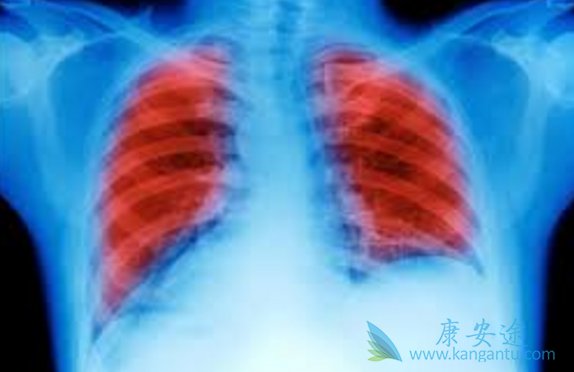

近年来,肺癌不再是老年人的专利,越来越多的年轻人也加入了肺癌的行列,甚至是不吸烟的年轻人。因早期肺癌大都无明显症状,有些患者甚至没有症状,导致很多人发现时已是中晚期。那么,肺癌晚期有多可怕?肺癌晚期临终前症状往往比较明显,常见的临终前症状有声嘶、胸痛、气促、发热、咳血等,给患者带来了很大的痛苦。那肺癌中晚期能活多久?

一旦被诊断为“肺癌晚期”,很多患者都陷入了无限的恐慌中,感觉死神即将到来。据统计,在肺癌的治疗中,超过70%的肺癌患者因没及时发现病情,导致晚期肺癌不能手术治疗。以肺癌第IV期为代表,若不及时治疗生存期大约在3-6个月。其实,肺癌晚期患者还能活多久并非一概而论。肺癌晚期患者只要积极治疗,也是能延长生存期的。

肺癌主要分为非小细胞肺癌和小细胞肺癌。非小细胞肺癌在术后发生复发转移的几率也比较高,手术后五年的非小细胞肺癌患者存活率分别:第I期为44.5%,第II期为36.1%,少部分第III A期则少于30%,越早治疗肺癌,患者的存活率就越高。而对于早期的小细胞肺癌患者来说,若是及时以手术切除联合生物治疗、放化疗,在没有肺癌淋巴转移的情形下,三年的存活率可达65%,五年存活率可达50%。